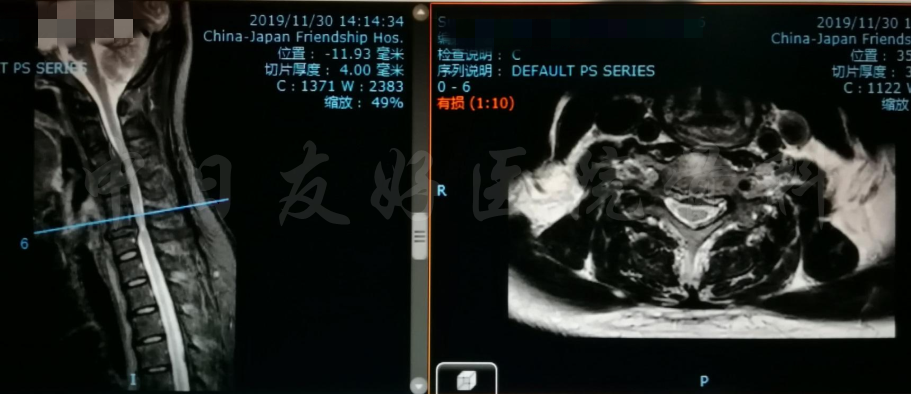

腰椎MRI

轴位MRI:腰3-4(左)、腰4-5(中)、腰5骶1(右)

2019年11月30日 颈椎MRI提示:颈3/4颈4/5颈6/7椎间盘突出,椎管狭窄;颈5-6水平脊髓异常信号,变性可能。

颈椎MRI

颈椎MRI

颈椎各节段MRI(上下滑动)